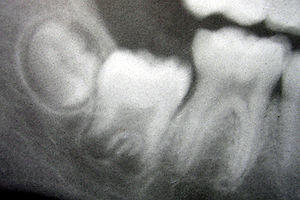

Although tooth eruption occurs at different times for different people, a general eruption timeline exists. Typically, humans have 20 primary (baby) teeth and 32 permanent teeth.[44] Tooth eruption has three stages. The first, known as deciduous dentition stage, occurs when only primary teeth are visible. Once the first permanent tooth erupts into the mouth, the teeth are in the mixed (or transitional) dentition. After the last primary tooth falls out of the mouth—a process known as exfoliation—the teeth are in the permanent dentition.

Primary dentition starts on the arrival of the mandibular central incisors, usually at eight months, and lasts until the first permanent molars appear in the mouth, usually at six years.[45] The primary teeth typically erupt in the following order: (1) central incisor, (2) lateral incisor, (3) first molar, (4) canine, and (5) second molar.[46] As a general rule, four teeth erupt for every six months of life, mandibular teeth erupt before maxillary teeth, and teeth erupt sooner in females than males.[47] During primary dentition, the tooth buds of permanent teeth develop below the primary teeth, close to the palate or tongue.

Mixed dentition starts when the first permanent molar appears in the mouth, usually at six years, and lasts until the last primary tooth is lost, usually at eleven or twelve years.[48] Permanent teeth in the maxilla erupt in a different order from permanent teeth on the mandible. Maxillary teeth erupt in the following order: (1) first molar (2) central incisor, (3) lateral incisor, (4) first premolar, (5) second premolar, (6) canine, (7) second molar, and (8) third molar. Mandibular teeth erupt in the following order: (1) first molar (2) central incisor, (3) lateral incisor, (4) canine, (5) first premolar, (6) second premolar, (7) second molar, and (8) third molar. Since there are no premolars in the primary dentition, the primary molars are replaced by permanent premolars.[49] If any primary teeth are lost before permanent teeth are ready to replace them, some posterior teeth may drift forward and cause space to be lost in the mouth.[50] This may cause crowding and/or misplacement once the permanent teeth erupt, which is usually referred to as malocclusion. Orthodontics may be required in such circumstances for an individual to achieve a straight set of teeth.

The permanent dentition begins when the last primary tooth is lost, usually at 11 to 12 years, and lasts for the rest of a person's life or until all of the teeth are lost (edentulism). During this stage, third molars (also called "wisdom teeth") are frequently extracted because of decay, pain or impactions. The main reasons for tooth loss are decay and periodontal disease.[51]